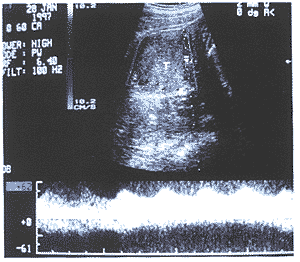

中国超声医学杂志990743 患者,女性,24岁。因怀孕后全身多毛、面貌改变26周入院。患者停经2个月左右出现 声音嘶哑,孕三个月左右出现痤疮、胡须、全身多毛。查体除上述表现外,尚可见皮肤色较 黑、乳晕不着色、腹无紫纹,考虑为雄激素增高所致。血激素检查:FSH 18.6mIU/ml, LH 180mIu/ml,PRL>200ng/ml,Ez>2000pg/ml,T>2000ng/dl,P>100ng/ml,即T(雄 激素)明显增高,应用Domier AI-5200型彩多普勒超声诊断仪,探头频率为5MHz,超声检查 表现:耻上见胎头,双顶径73mm,见胎心胎动,股骨长53mm,胎盘位于后壁,厚28mm,羊水 最大前后径50mm。子宫右侧附件区见50mm×52mm×65mm稍强实质肿块回声,边界清,有包膜 ,内回声欠均匀(图1),左侧附件区未见明显肿块回声。CDFI:胎儿脐带血流A/B比值为3.8 ,右侧附件肿块周边及内部均见丰富的彩色血流,呈红蓝相间的点、条状彩色血流回声(图2 ),肿块一动脉频谱为Vmax 55cm/s,Vmin 31cm/s,RI 0.43,为高速低阻血流(图3)。超声 提示:1.右侧附件实质性肿块(具分泌功能之卵巢肿瘤);2.单胎头位。患者继续怀孕至38 W+2天,行剖腹产及卵巢肿瘤切除术,剖出一正常男婴,出生时有轻度窒息,羊水 过少。术中见右卵巢肿瘤大小6cm×5cm×4cm,包膜完整,质硬。病理诊断:(右)附件卵巢 支持-间质细胞瘤(高、中度分化)。肿瘤部分区域瘤组织呈腺瘤状结构,衬以葵花子样核的 支持细胞,大部分区域呈片状排列的间质细胞。

图3 测量肿块-动脉频谱,为高速低阻型频谱